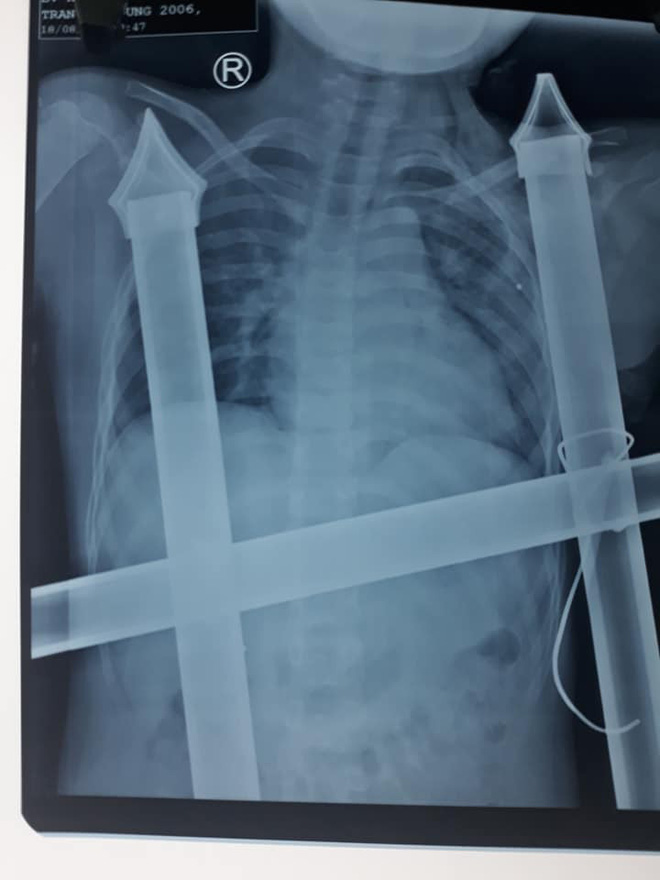

Theo bác sĩ CK.I Hồ Thái Phúc, Khoa Phẫu thuật tim mạch lồng ngực, Bệnh viện Hữu nghị Đa khoa Nghệ An cho biết, qua hình ảnh phim X-quang, các bác sĩ xác định vết đâm của ngạnh sắc nhọn hàng rào đã chạm tới nền đầu của bệnh nhân.

Hình ảnh chụp X-quang.

“Rất may mắn là vật sắc nhọn không làm mạch máu lớn và nội tạng bị tổn thương. Bệnh nhân bị đứt cơ ngực lớn, cọc sắt hàng rào tạo nên đường hầm trong khoang ngực kéo dài trên 10cm. Chúng tôi đã rút được dị vật ra khỏi cơ thể cậu bé an toàn. Đồng thời, lau rửa, sát trùng vết thương, dẫn lưu đường hầm, khâu cơ ngực lớn và da liền lại”, BS. Phúc cho biết thêm.